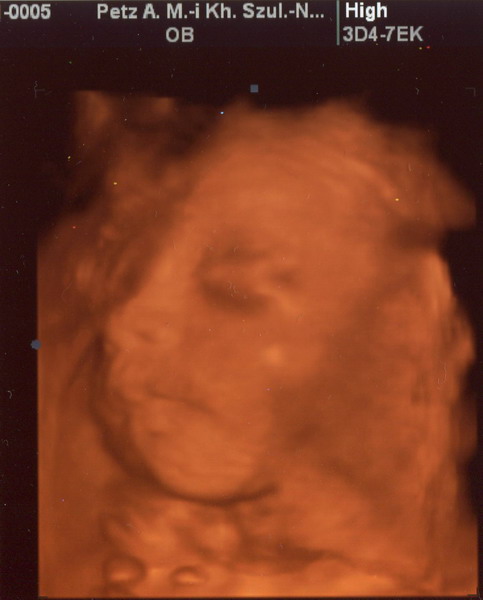

Gergő:

Kép

Majdnem egyforma a két kép amit kaptunk, de azért remélem nem baj, hogy mindegyiket megmutatom. :D

Na, szóval minden a helyén van, csuda édes pofa volt Gergő. Már 1160 g körül van a súlya, ami miatt azt mondták, hogy valószínűleg idősebb a megállapított kornál. (vagy ő is jó nagy lesz... :shock: ) De szerintem is idősebb lehet, hisz ezt támasztja alá az is, hogy a ciklusom 26. napján pozi lett a 25-ös erősségű terhességi tesz, meg a 12. heti uh szerint is nagyobb volt kb 4 nappal a kiírtnál.

Amúgy az elején még mutatta a kis pofiját, de aztán egy idő után hátat fordított... De szerencsére láttuk ahogy nyitogatta a szemét, játszott a lábujjaival, a kezét a szájába vette, számlálgatta az ujjacskáit és mozgatta a kis száját. :D amikor hátat fordított, az is látszott, hogy a tarkóján van haja! :D Bencének is pont ott volt sok haja amikor megszületett, a feje tetején kevés volt neki, de ott lent elég sok. Úgyhogy ebben legalább is hasonlít bátyusra!

Jaj Lányok, én annyira boldog vagyok!!!!!!!!!!!!!!!!!!!!!!!!!!!!!!!!!!!!